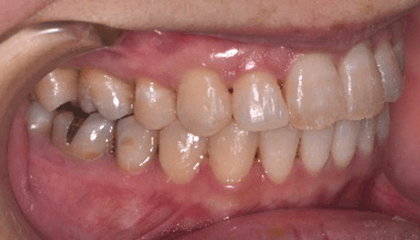

治療後

特に前歯が噛んでいない状態と八重歯は奥歯に負担がかかり、むし歯や歯周病が進行しやすい噛み合わせです。

下の前歯が、先天的に1本少ない患者さんです。上下の歯の本数が違うために、右上犬歯が八重歯になっています。

動的期間1年半で終了です。

ブラケットを外しました。上は着脱式の保定装置、下は前歯の裏側で保定しています。